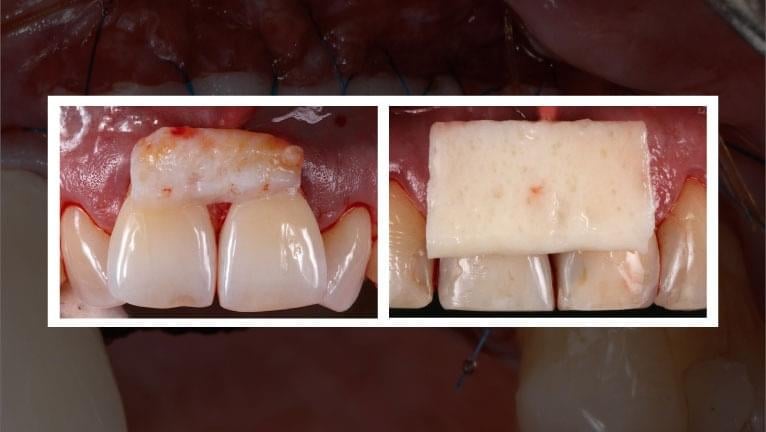

SOFT TISSUE MANAGEMENT IN DENTISTRY- PREDICTABLE SYSTEMS AND TECHNIQUES

Join Dr. Naheed Mohamed and Dr. Stephen Phelan for a free webinar training that will teach you how to be confident and successful with your soft tissue grafting procedures. Learn 6 different types of soft tissue grafts and different harvesting locations and techniques.

This webinar will feature actual cases from Dr. Mohamed’s specialty practice. The presentation will focus on a systematic approach to treatment planning and executing a successful soft tissue grafting procedure.